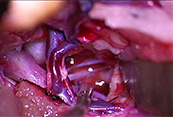

医療系

大学病院、総合病院などの手技収録 をはじめ各領域の医学学会学術集会の撮影。ライブ映像の配信、医薬品メーカー、医療機器メーカーなどの機器マニュアル撮影など全国どこでも対応可能です。

循環器内科及び脳神経外科のカテーテル治療ライブ中継・手技収録を得意としています。

倉敷PCIライブデモンストレーションコース(倉敷中央病院:循環器内科)のライブ映像収録・メディア販売を16年、小倉ライブ(小倉記念病院:循環器内科)のライブ中継・収録など多くの経験から、参加者が見たい映像を的確に、またタイミング良くセレクトしながら確実な中継を実行、収録を提供できます。